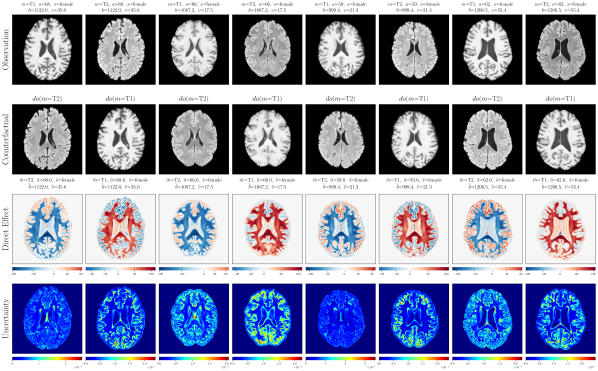

4.2 Brain Imaging Counterfactuals

To demonstrate our model’s ability to produce faithful high-fidelity counterfactuals of real data, we extend our approach to a real-world scenario involving brain MRI scans from the UK Biobank (Sudlow et al., 2015). As before, we start with an assumed causal generative process involving a set of observed variables as shown in Figure 4(a). The causal graph is medically informed and extends the scenario in Pawlowski et al. (2020) by: (i) introducing an additional MRI Sequence (T1/T2) binary variable to enable discrete counterfactuals; (ii) having directly. We used a scaled-up version of our exogenous prior HVAE as ’s mechanism and used (conditional) normalizing flows for the other mechanisms (see Appendix A.1). As shown in Figure 4, our deep SCM is capable of producing qualitatively sharp counterfactuals with localised changes according to the intervened upon parent(s) and the associated causal graph. Importantly, the identity of subjects is well preserved in all cases including null-interventions (i.e. nothing). Table 2 shows the counterfactual effectiveness results from random interventions on each variable. We observed satisfactory initial counterfactual effectiveness and significant improvements of post counterfactual training, demonstrating the merit of the proposed approach. Please refer to Appendix A.2 for notes on abduction uncertainty and D for additional results.

‘MRI Seq.’ counterfactuals

Post counterfactual training:

‘Sex’ counterfactuals

D.3 Extra Results